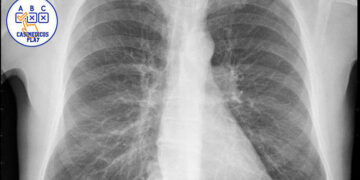

Introducción y descripción del caso

Mujer de 34 años. Es dependienta de una tienda de modas. El único antecedente clínico es artritis reumatoide desde hace 5 años, controlada con metrotrexate y sin brotes desde hace 2 años. No tiene hábitos tóxicos. Al final de una consulta rutinaria, refiere que desde hace 3 días presenta dolor abdominal bajo de tipo cólico, de intensidad leve, no relacionada con un cambio de habito intestinal, ni con trasgresión dietética, ni con alteración menstrual.

Se observa una perdida de peso leve,( 3 kg), en los últimos tres meses, aunque refiere que lleva mucho estrés en el trabajo y come mal. No presenta síndrome miccional ni fiebre ni otras sintomatologías. La exploración abdominal es anodina, se solicita hemograma y bioquímica general, test de sangre oculta en heces. Se pauta dieta y espasmolíticos, y observación domiciliaria. Al día siguiente vuelve a consultar por el dolor abdominal, aunque refiere que es más intenso, y que se va acompañado de nauseas y un vomito, y una deposición blanda con hebras de sangre. En la exploración abdominal presenta un abdomen poco depresible, dolor en fosa iliaca derecha, con Signo de blumberg positivo, por lo que se remite a Urgencias hospitalarias con diagnostico de abdomen agudo. Es valorada por el cirujano decidiéndose intervención quirúrgica, detectándose un plastron inflamatorio abscesificado a nivel de ileon distal y colon proximal, se hace resección parcial, siendo dada de alta 10 días después. Actualmente lleva 3 meses estable y sin nueva crisis.

La exploración abdominal es anodina, se solicita hemograma y bioquímica general. El test de sangre oculta en heces es negativo y en la analítica general, se percibe una discreta anemia microctica e hipocrómica. Ecografía abdominal: plastrón inflamatorio en FID que engloba apéndice y colon ascendente.